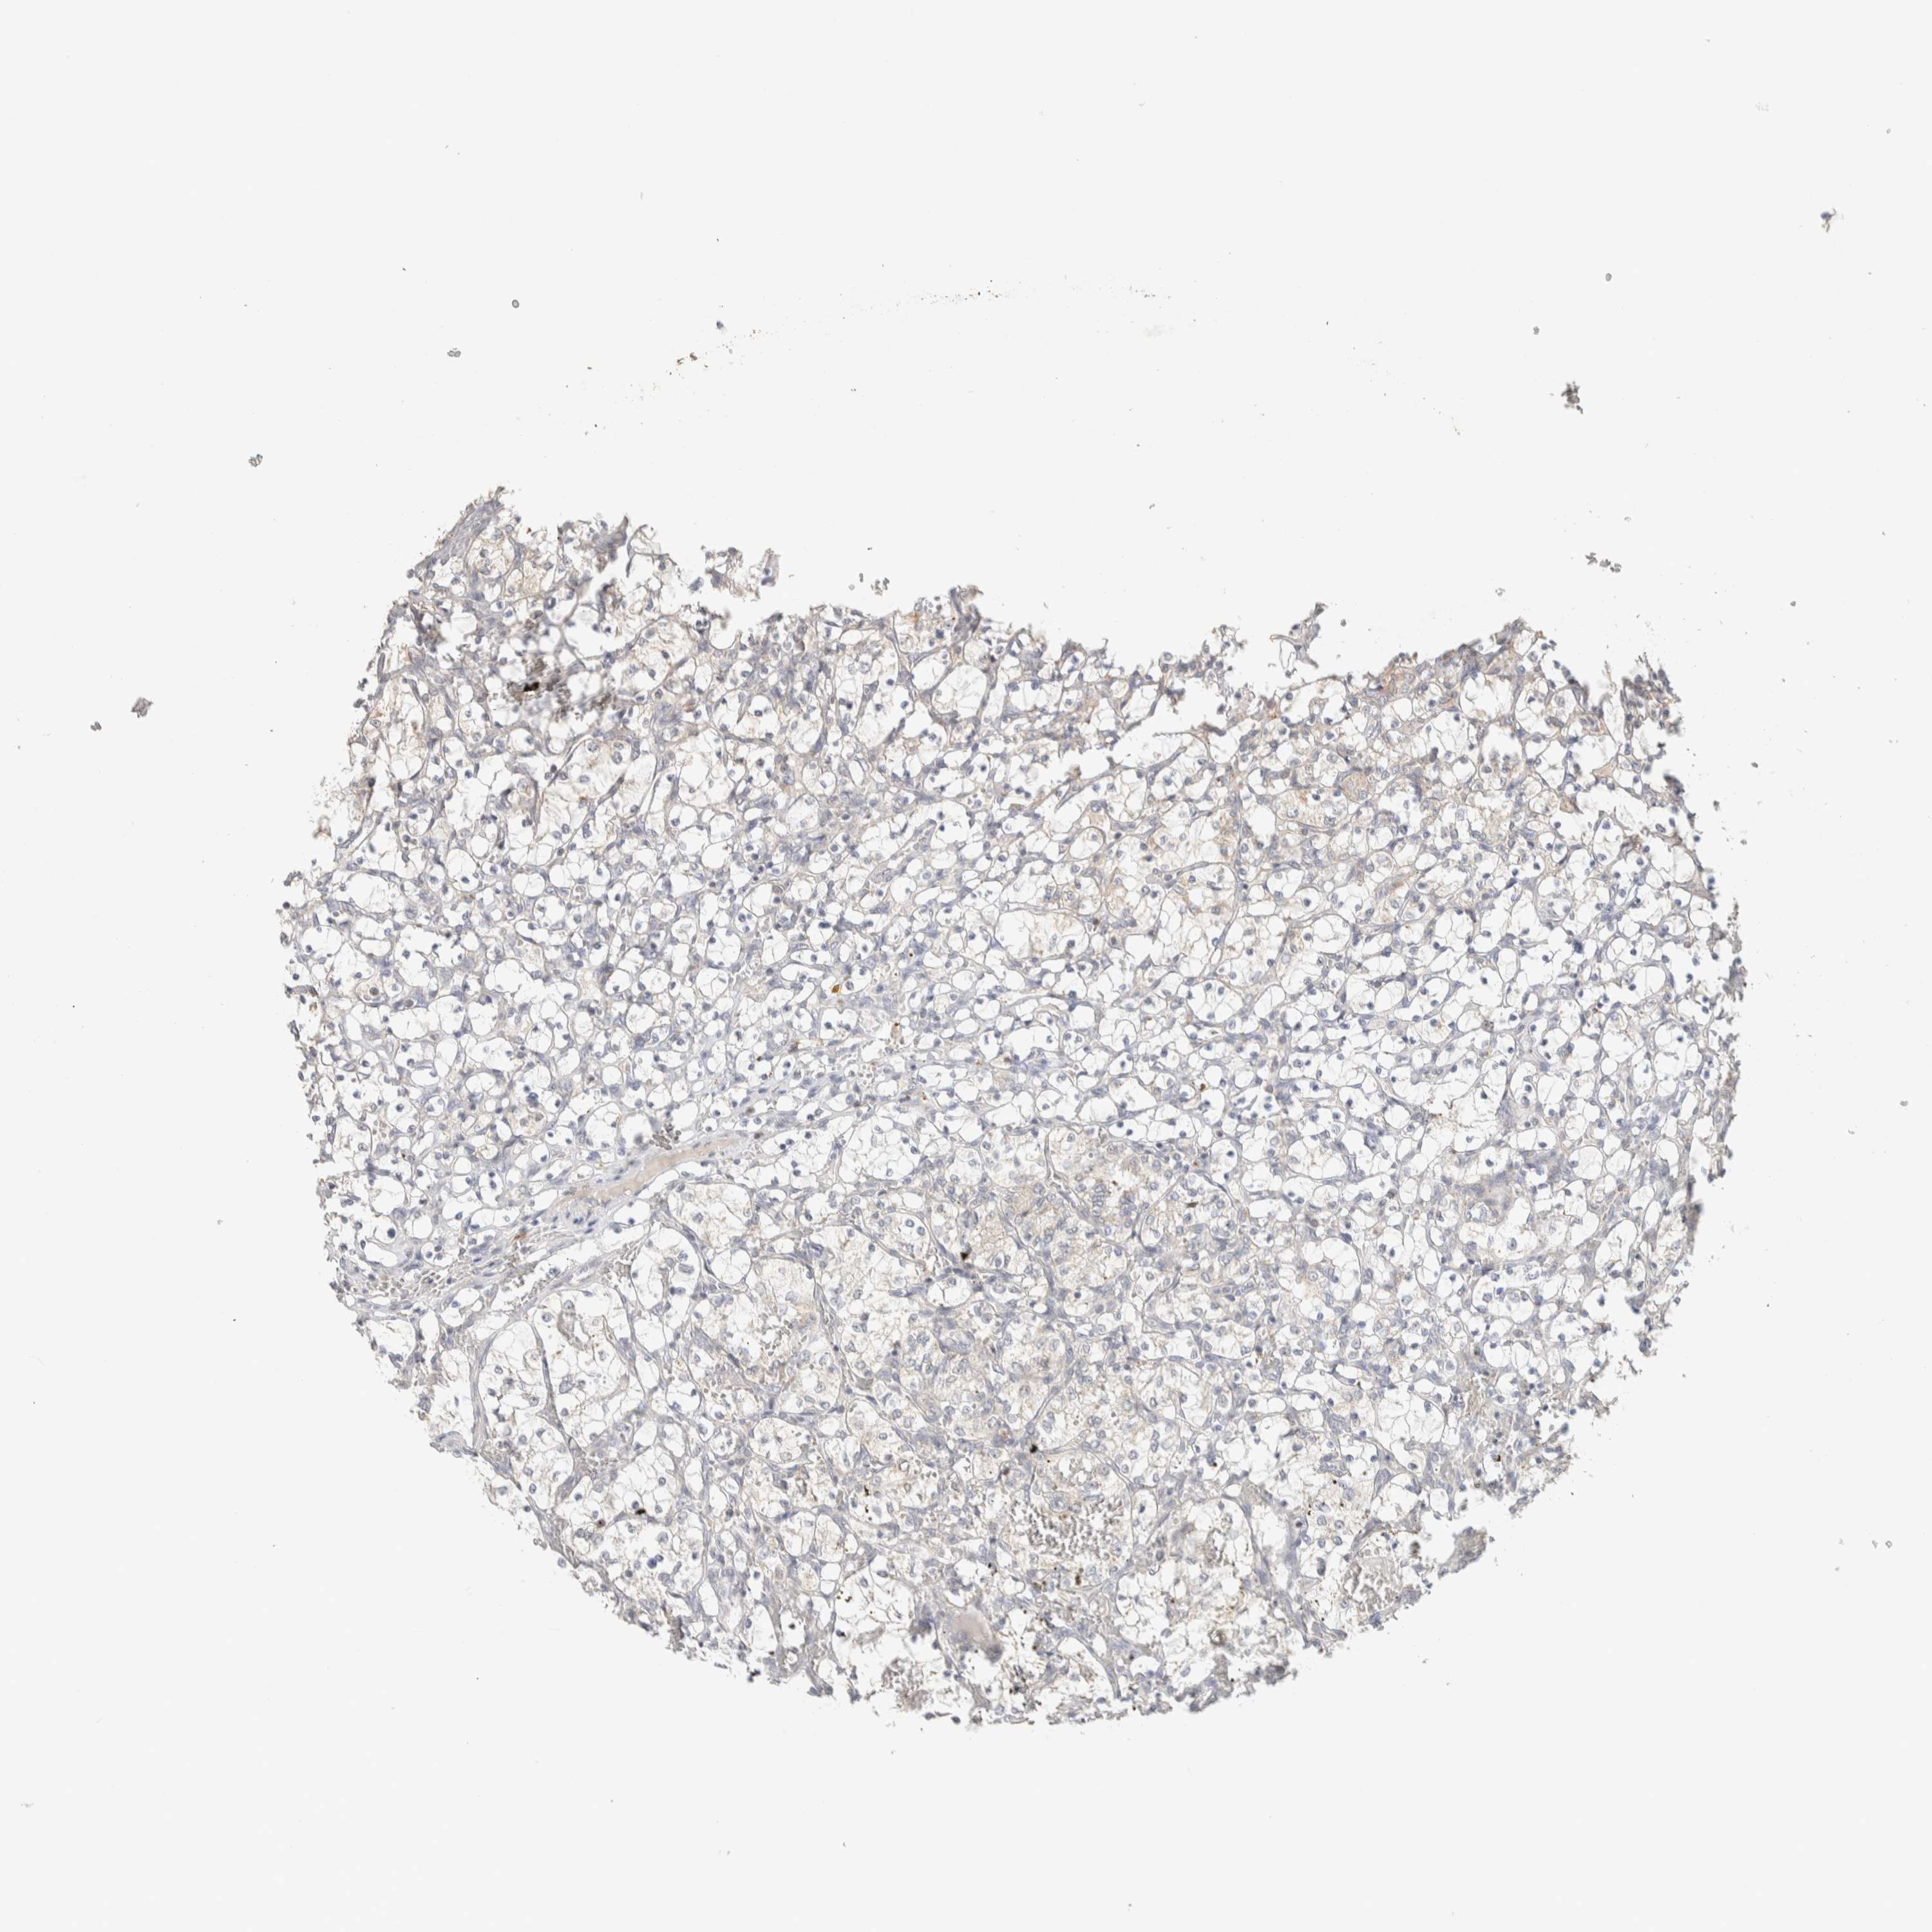

KIDNEY RENAL PAPILLARY CELL CARCINOMA (TCGA) - Interactive survival scatter ploti

The Survival Scatter plot shows the clinical status (i.e. dead or alive) for all individuals in the patient cohort, based on the same data that underlies the corresponding Kaplan-Meier plots. Patients that are alive at last time for follow-up are shown in blue and patients who have died during the study are shown in red.

The x-axis shows the expression levels (FPKM) of the investigated gene in the tumor tissue at the time of diagnosis. The y-axis shows the follow-up time after diagnosis (years). Both axes are complimented with kernel density curves demonstrating the data density over the axes. The top density plot shows the expression levels (FPKM) distribution among dead (red) and alive patients (blue). The right density plot shows the data density of the survived years of dead patients with high and low expression levels respectively, stratified using the cutoff indicated by the vertical dashed line through the Survival Scatter plot. This cutoff is automatically defined based on the FPKM cutoff that minimizes the p-score. The cutoff can be changed by dragging the vertical line or by entering a cutoff value in the square labeled "Current cut-off".

Under the Survival Scatter plot the p-score landscape (black curve; left axis) is shown together with dead median separation (red curve; right axis). Dead median separation is the difference in median mRNA expression between patients who have died with high and low expression, respectively. It is calculated as follows: median FPKM expression of dead patients with high expression - median FPKM expression of dead patients with low expression. This is intended to aid the user in visually exploring custom cutoffs and the associated p-scores and dead median separation.

Individual patient data is displayed and can be filtered by clicking on one or more of the category buttons on the top of the page. Categories describing expression level and patient information include: high, low, alive, dead, female, male and tumor stages. The scale of the x-axis can be toggled between linear and log-scale by clicking on the "x log" button. Mouse-over function shows TCGA ID, patient information and mRNA expression (FPKM) for each patient.

& Survival analysisi

Kaplan-Meier plots summarize results from analysis of correlation between mRNA expression level and patient survival. Patients were divided based on level of expression into one of the two groups "low" (under cut off) or "high" (over cut off). X-axis shows time for survival (years) and y-axis shows the probability of survival, where 1.0 corresponds to 100 percent.

ITPA is not prognostic in Kidney Renal Papillary Cell Carcinoma (TCGA)